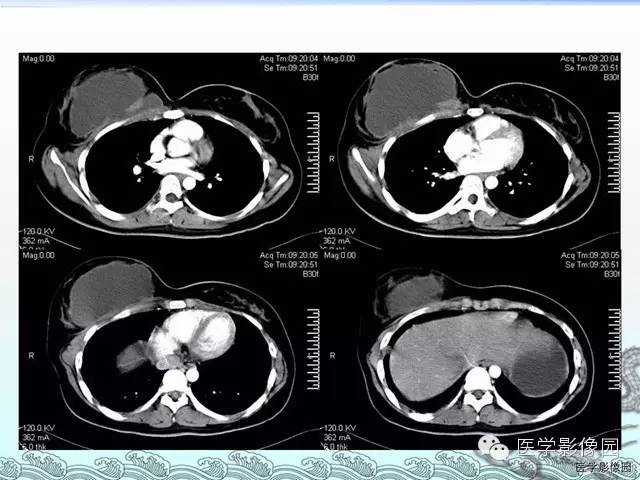

胸壁结核1例影像表现

【病例】胸壁结核1例影像表现